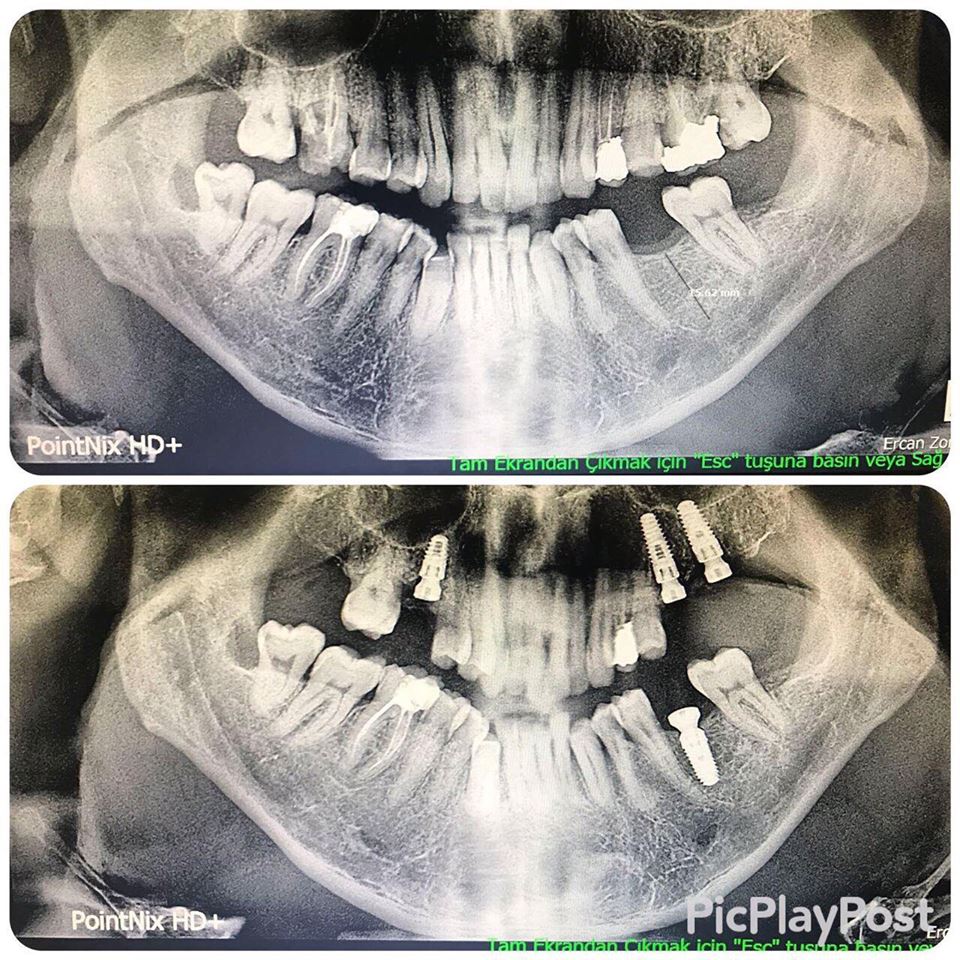

İMPLANT TEDAVİSİ

implant tedavisi